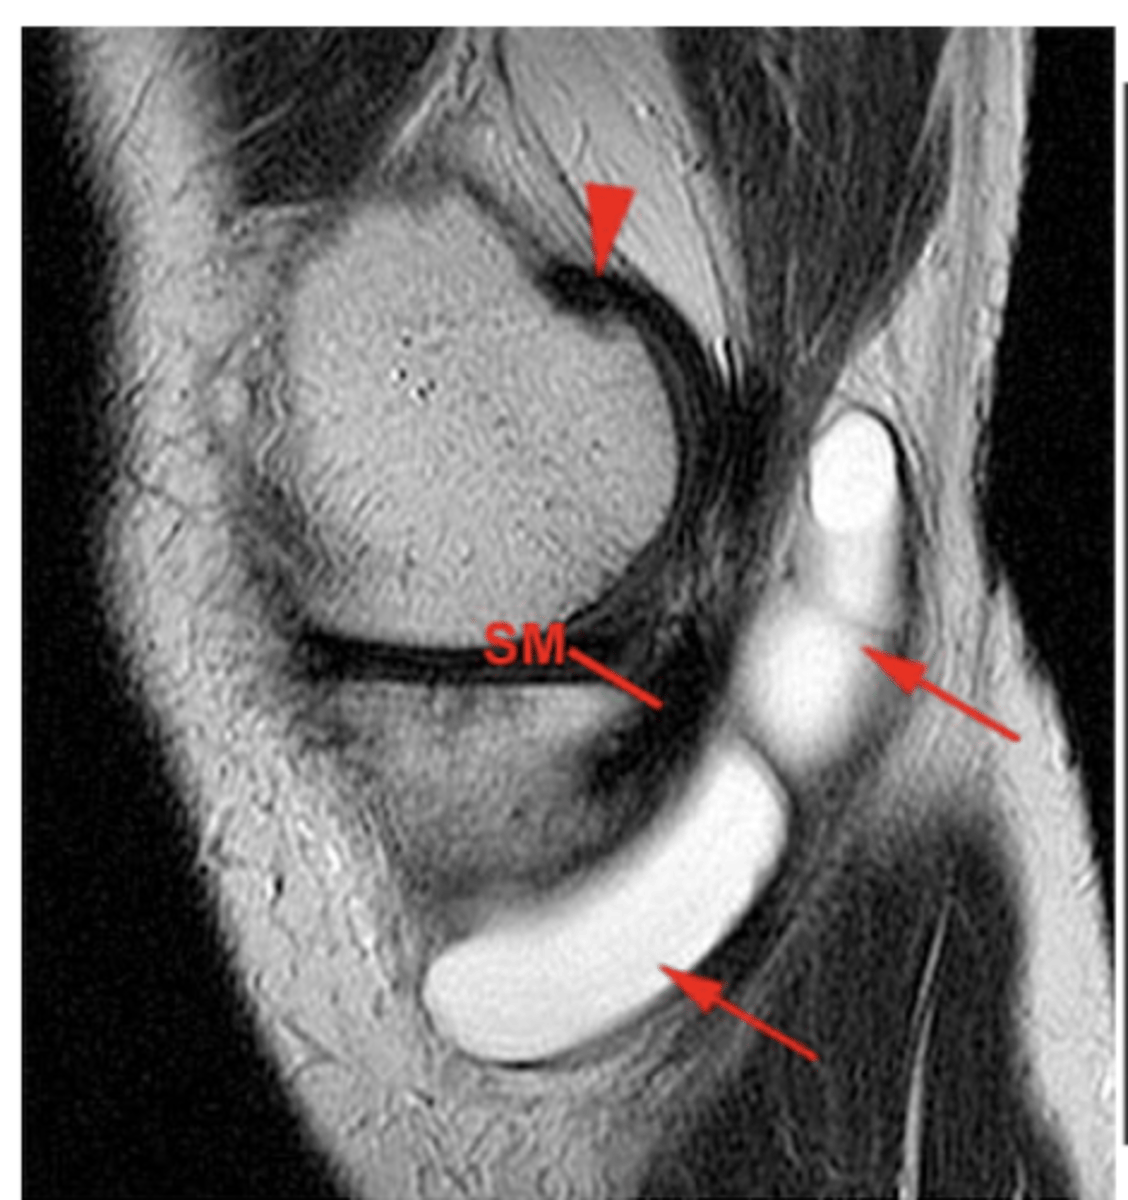

Popliteus injury

Define the pathology.